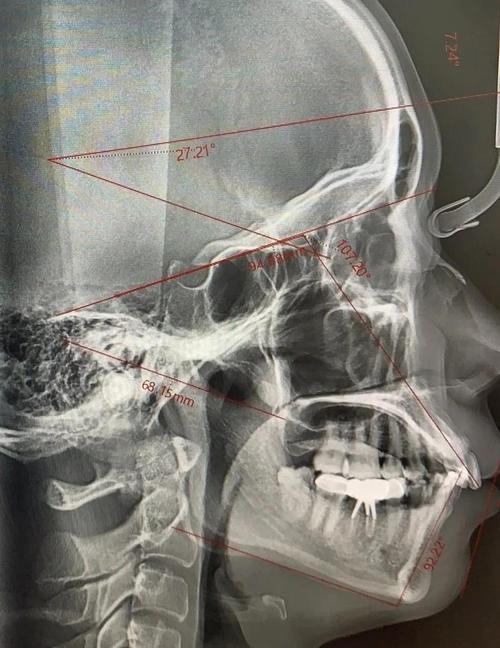

- 关键测量: 头颅侧位片是进行骨骼分析和牙齿分析的基础,包含大量重要的测量指标(如ANB角、SNA角、SNB角、上下颌长度、牙齿倾斜度、拥挤度等),为制定精确的治疗计划提供客观依据。

- 头颅侧位片: 正畸诊断和计划制定的核心,用于骨骼分析、牙齿分析、软组织测量、预测治疗效果、判断是否需要正颌手术。